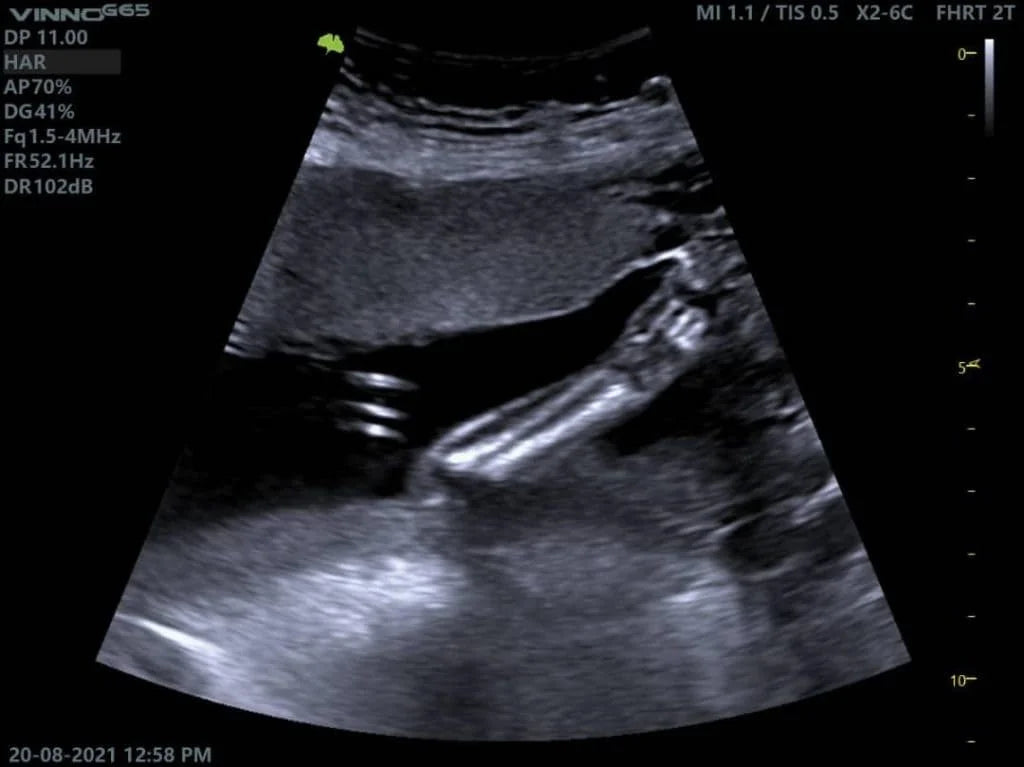

El ultrasonido abdominal se ha convertido en una herramienta indispensable en la medicina moderna para la evaluación del tracto digestivo. En la imagen destacada, capturada con un equipo VINNO G65, se puede apreciar la precisión con la que este método nos permite obtener información crucial sobre el estado de los órganos abdominales.

Los ecógrafos VINNO, como el VINNO G65, incorporan tecnología de alta resolución que proporciona imágenes nítidas y detalladas del tracto digestivo. Su capacidad Doppler permite evaluar el flujo sanguíneo en órganos clave, mejorando la detección de anomalías vasculares y procesos inflamatorios.

El ultrasonido abdominal es una herramienta esencial para evaluar el tracto digestivo, ya que proporciona imágenes en tiempo real sin la necesidad de procedimientos invasivos. Además de detectar obstrucciones intestinales, inflamaciones y tumores, este método también permite evaluar el flujo sanguíneo en órganos abdominales mediante el Doppler color, lo que es clave para identificar anomalías vasculares.

Gracias a la tecnología avanzada de equipos como el VINNO G65, se obtiene una visualización más detallada de los órganos, permitiendo diagnósticos más precisos y tratamientos oportunos. Esto convierte al ultrasonido en un pilar fundamental en la evaluación de trastornos digestivos y en la prevención de complicaciones graves.